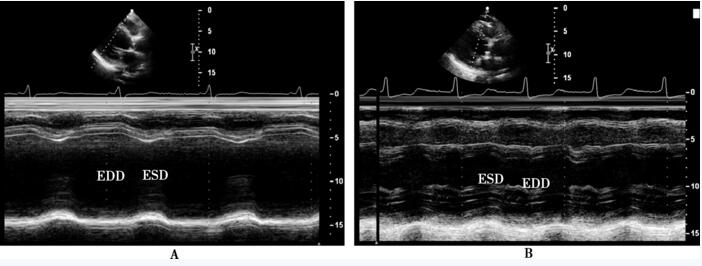

图65-3 术前、术后超声心动图在心室大小比较

A:术前,M型超声心动图显示左心室舒张末期(83mm)、收缩末期内径(67mm)明显扩大; B:术后3个月,M型超声心动图显示左心室舒张末期内径(67.8mm)、收缩末期内径(57mm)增大,但较术前明显减小。ESD:收缩末期内径;EDD:舒张末期内径